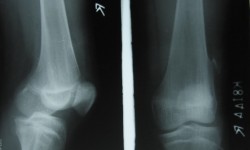

Osteo poikilosis with Osteopathia striata (Overlapping syndromes)

By Admin | September 30, 2013 - 7:23 am | Musculoskeletal, Skeletal Dysplasias

Both knee-A P View

OSTEOPATHIA STRIATA ( VOORHOEVES DISEASE)

By Admin | September 29, 2013 - 1:42 pm | Musculoskeletal, Skeletal Dysplasias

Rt. Knee A.P and Lateral